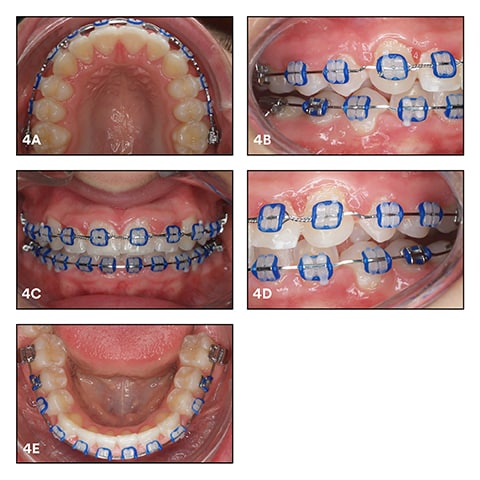

Another seven weeks later, we integrated a 0.017 x 0.025" SS archwire. During the following appointment in September, some finishing steps were added between the canines and the first premolars in both jaws for extrusion and anchorage (Fig. 4). In the maxilla, a steel ligature in a figure-eight pattern was applied under the archwire from canine to canine (13 to 23) to avoid gap opening during the start of treatment with Class-II elastics. We continued with Class-II elastics, followed by Class II with an up-and-down component until March 2016. See Figure 4a-e.